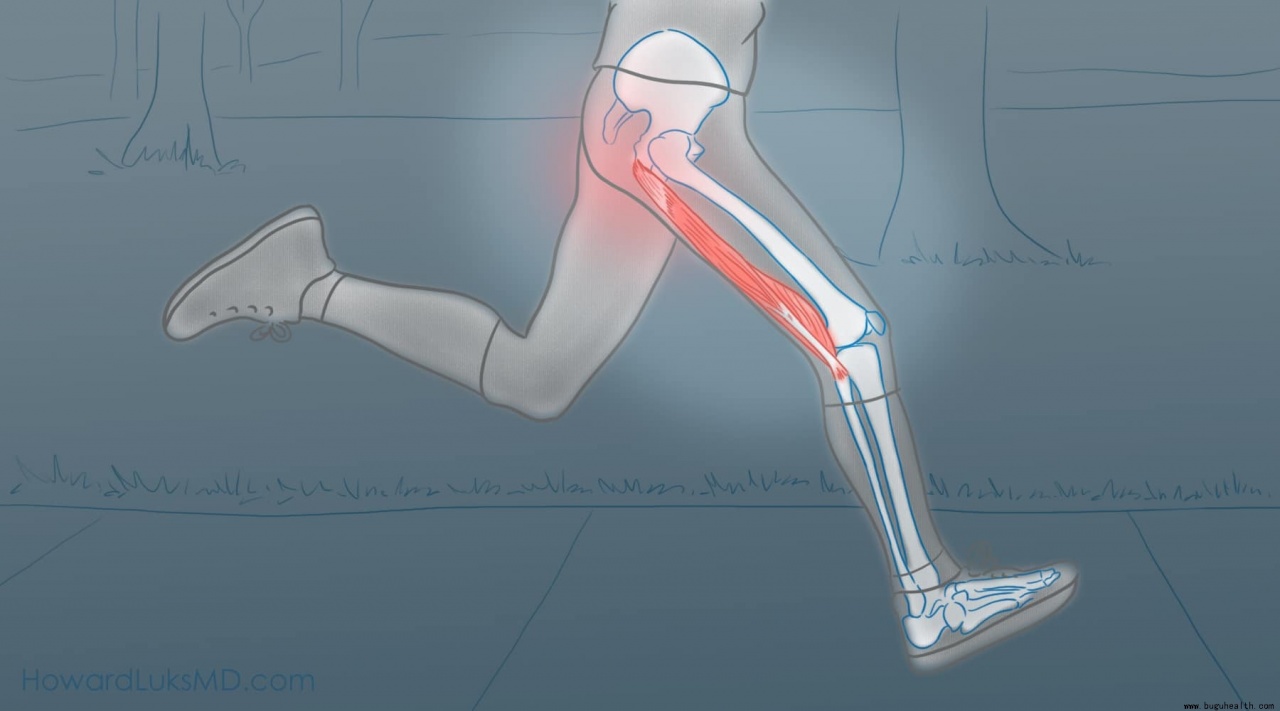

损伤机制:离心收缩下的“刹车”失控

腘绳肌损伤多发生于高速运动中的急停或变向瞬间。此时肌肉处于被拉长同时仍需发力的“离心收缩”状态,当负荷超过肌纤维承受极限,即发生撕裂。东契奇标志性的后撤步与突破急停,是该部位的高风险动作。